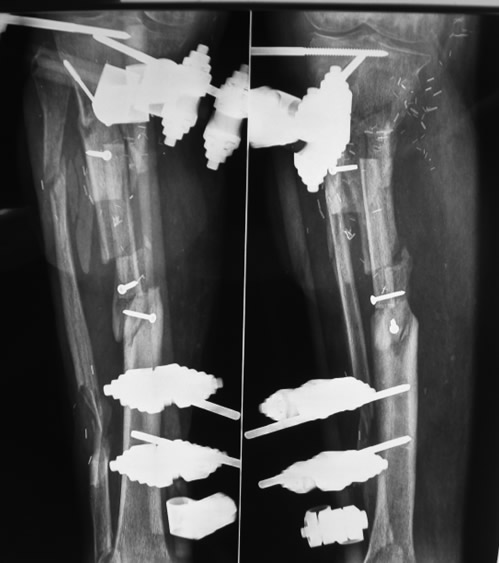

Paso 3: Reconstrucción de defecto óseo de tibia

Se reconstruyó el defecto óseo con una transferencia microquirúrgica de peroné osteocutáneo contralateral.

Paso 4: Fijación esquelética definitiva

Se retiró el fijador externo a los dos meses y se sustituyó por una placa de osteosíntesis para permitir la rehabilitación simultánea de la rodilla.